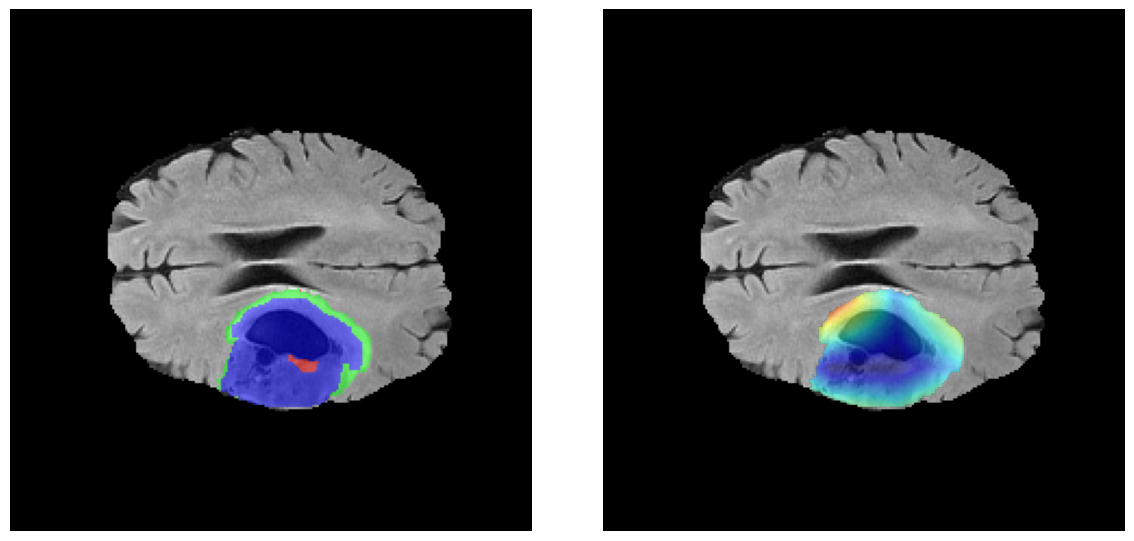

Mapas de Explicabilidad (Grad-CAM++)

Visualización de las regiones de atención del modelo que validan su razonamiento clínicamente relevante

Ejemplos HGG - Atención en Núcleo Necrótico y Tumor Realzado

HGG Grad-CAM++ 1 HGG Grad-CAM++ 2 HGG Grad-CAM++ 3 HGG Grad-CAM++ 4 HGG Grad-CAM++ 5 HGG Grad-CAM++ 6

Los heatmaps muestran que el modelo concentra su atención en las regiones de Tumor Realzado (rojo) y Núcleo Necrótico (azul), características patológicas clave de los gliomas de alto grado.

Validación con IA Explicable

El análisis Grad-CAM++ reveló que el modelo desarrolla automáticamente la capacidad de localizar las regiones tumorales. Para casos HGG, la atención se alinea fuertemente con las regiones de Tumor Realzado (ET) y Núcleo Necrótico (NCR). En contraste, los casos LGG muestran atención más difusa, principalmente concentrada en la región de Edema Peritumoral (ED), lo cual es consistente con la patofisiología conocida de los gliomas.

✅ Validación con IA Explicable